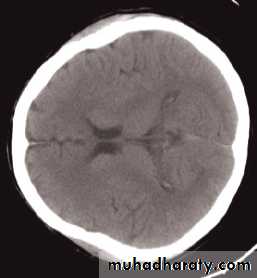

Computed tomography of the brain

• A routine CT examination of the brain involves making 20–30 axial sections.

• The axial plane is the routine projection but computer reconstructions can be made from the axial sections, which then provide images in the coronal or sagittal planes

• The window settings are selected for the brain and are also altered to show the bones

The cardinal signs of an abnormality on a CT scan are:

• Abnormal tissue density• Mass effect

• Enlargement of the ventricles.

Abnormal tissue density

• Abnormal tissue may be of higher or lower density than the normal surrounding brain.• High density is seen with recent haemorrhage, calcified lesions, and areas of contrast enhancement

• Low density is usually due to neoplasms or infarcts, or to oedema, which commonly surrounds neoplasms, infarcts, haemorrhages and areas of inflammation.